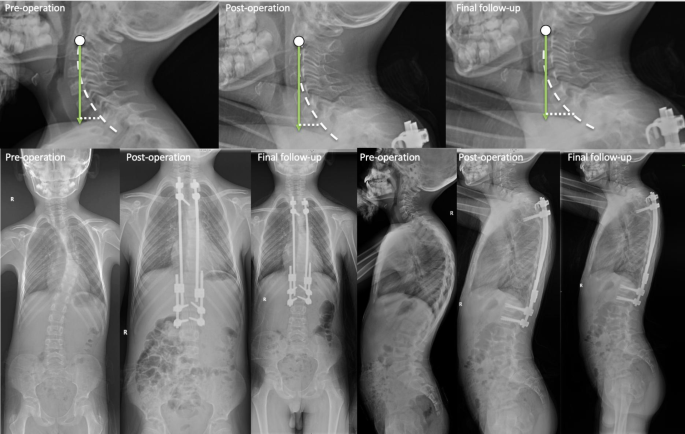

After inserting the growing rod, C2-C7 CL, T1 slope, and C2-7 SVA showed no significant change after surgery in the short term. However, in the final follow-up, C2-C7 CL, T1 slope, and C2-7 SVA increased from − 16.93 ± 10.73° to -35.45 ± 15.69°, 27.81 ± 12.95°to 41.86 ± 19.71° and 16.08 ± 11.23 mm to 23.32 ± 13.63 mm respectively (P < 0.05) (Fig. 2.) Cervical sagittal alignment changes after the growing rod surgery, as illustrated in Fig. 3.

Patients who were diagnosed with PJK had a larger C2-C7 CL and T1 slope (28.57 ± 12.43 vs. 13.35 ± 7.76, P < 0.001; 28.50 ± 11.00 vs.7.07 ± 13.50, P < 0.001). The number of growing rods and location of upper instrumented vertebrae (UIV) had no significant influence on the sagittal cervical parameters. (P > 0.05)(Fig. 4). A typical case who suffered a cervical sagittal imbalance caused by PJK is shown in Fig. 5. A case with no PJK and the sagittal cervical alignment kept balanced, as shown in Fig. 6.

During growing rod treatment, the cervical sagittal balance changes in the patient without PJK. (It is a 10-year-old male patient diagnosed with idiopathic EOS. After the 2nd distraction, scoliosis and hyperkyphosis are corrected well. In the final follow-up, he does not have PJK above the growing rod. Sagittal cervical alignment change: C2-C7 CL increases from 57.9° to 62.9°, T1 slope increases from 48.1° to 57.4°, and C2-C7 SVA increases from 22.5 mm to 24.5 mm.)